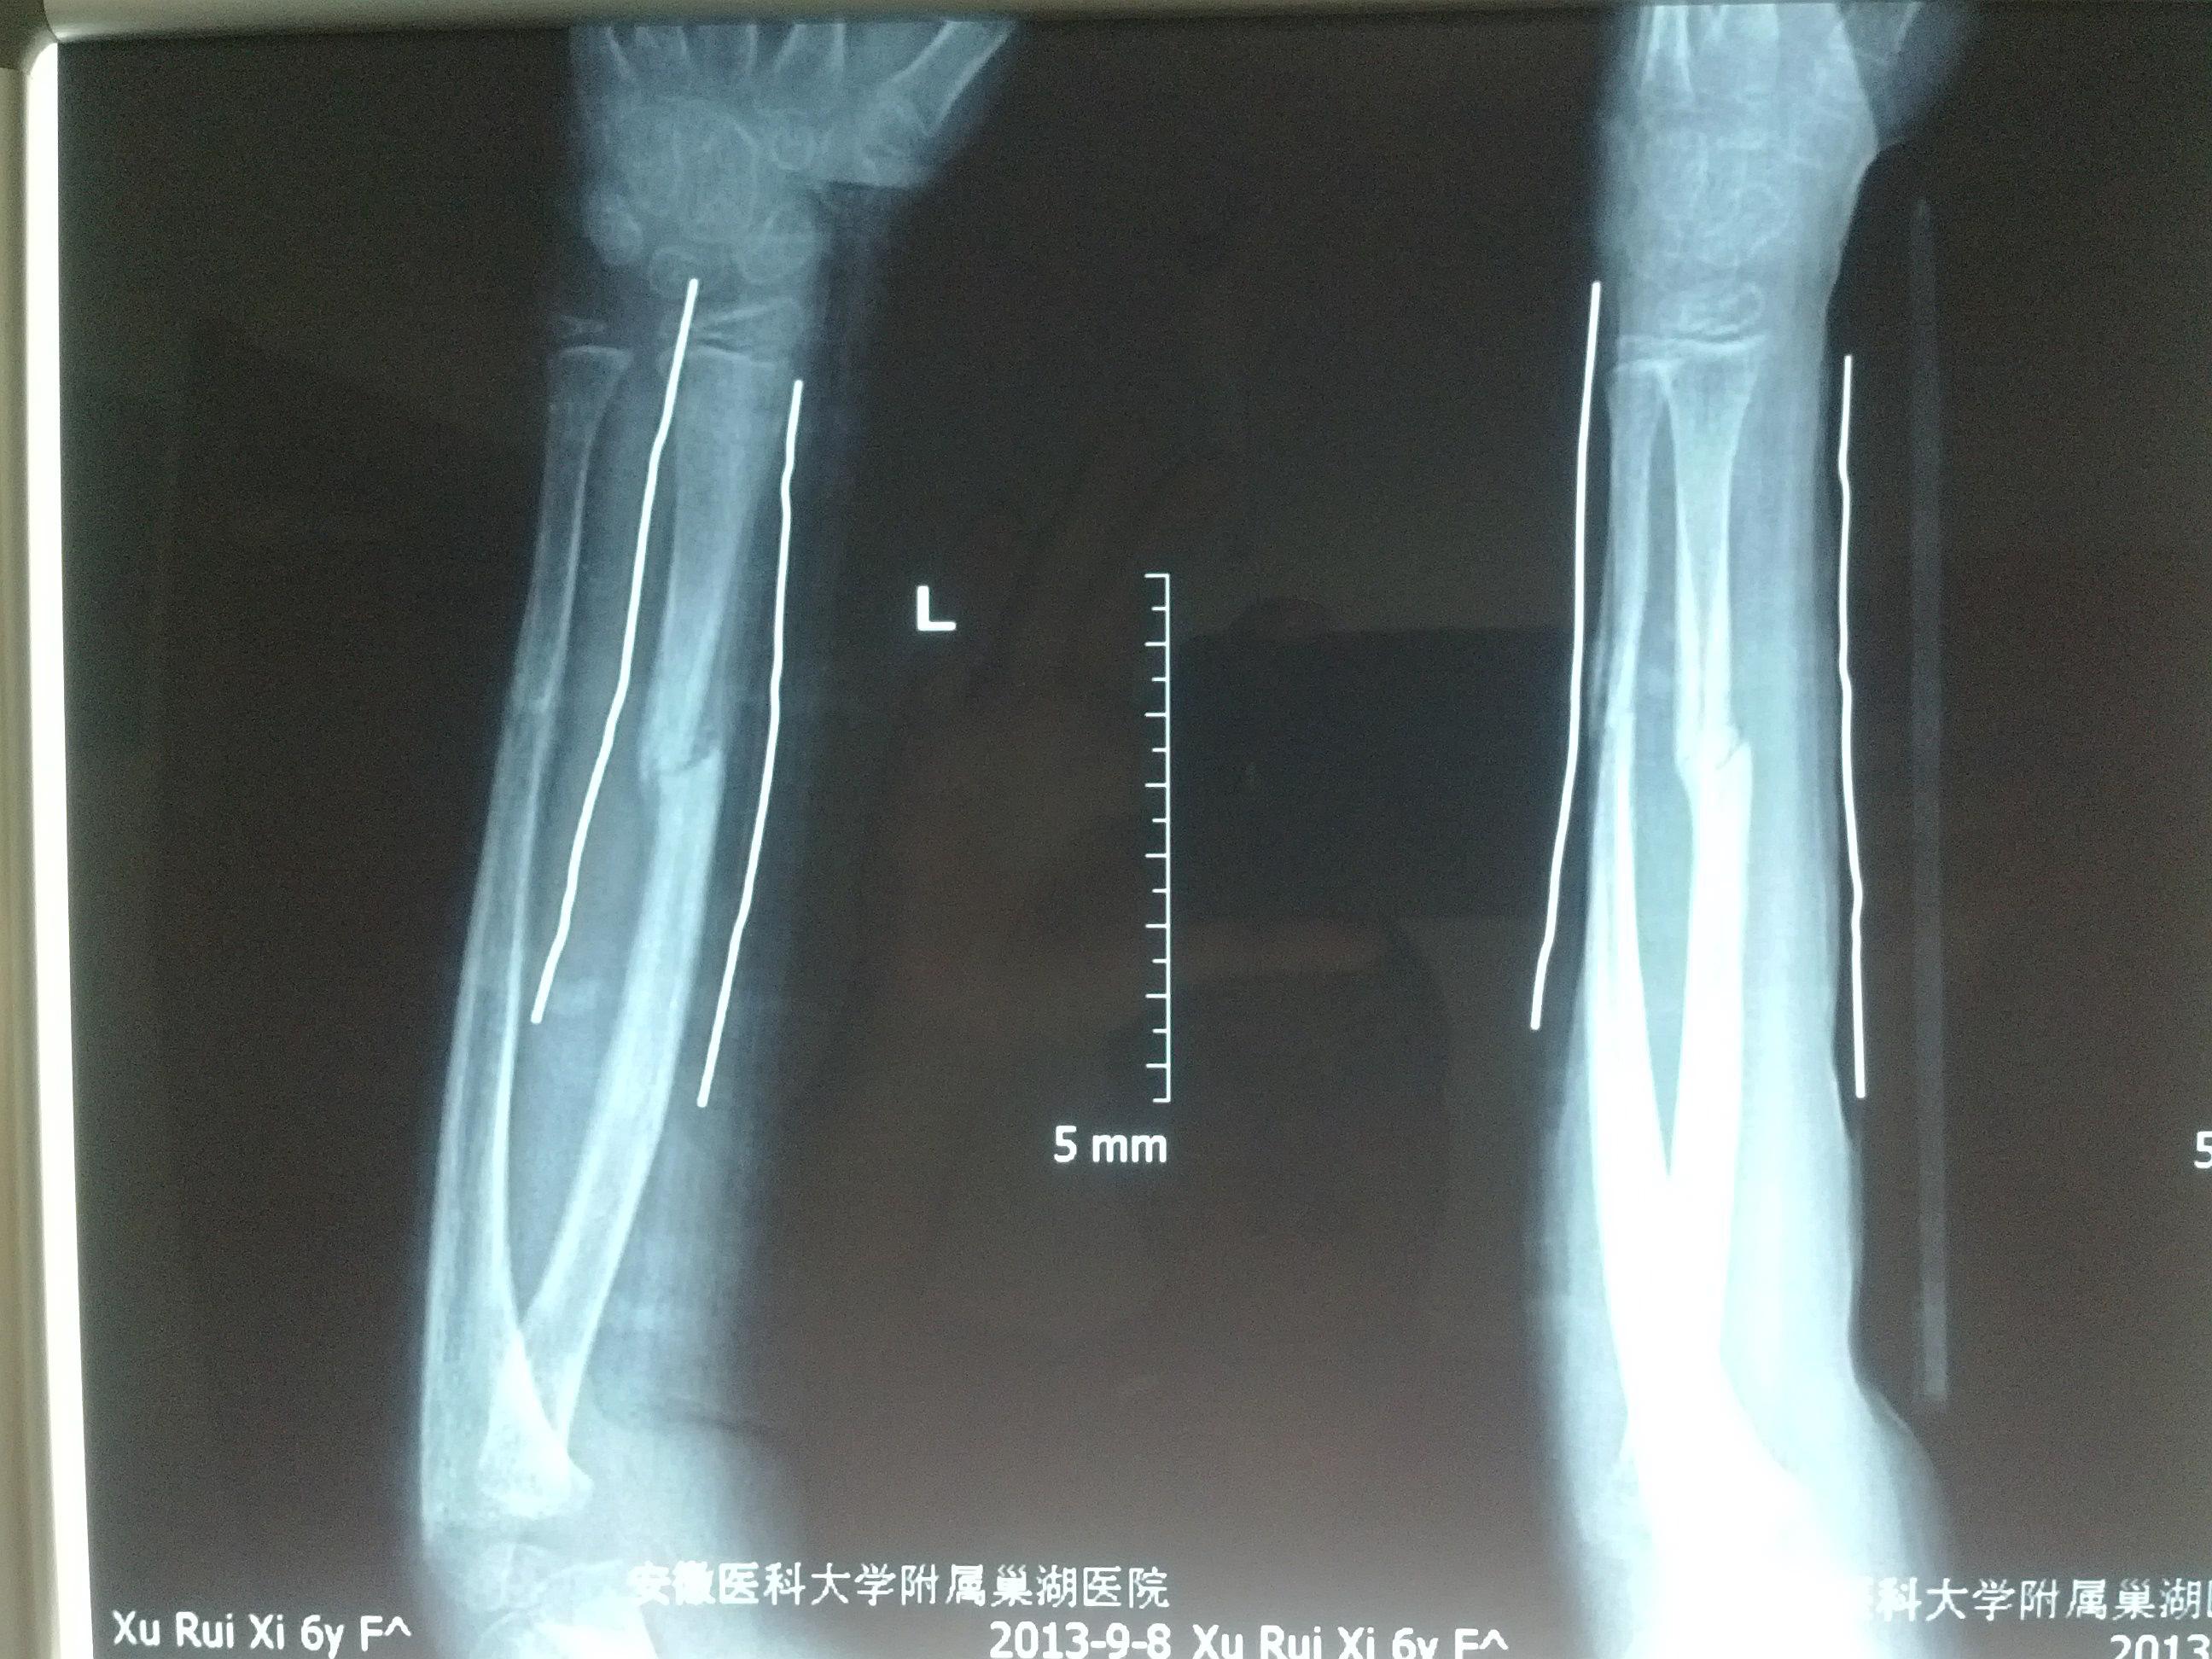

左尺桡骨双骨折

请各位老师看看此尺桡骨双骨折现状如何